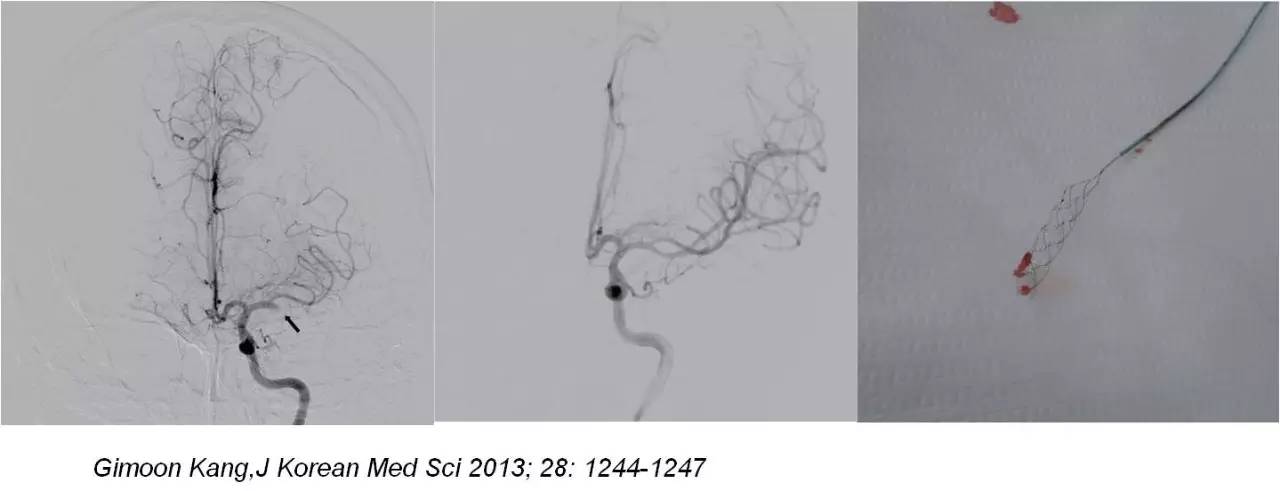

》若无再通,微导丝缓慢推进通过闭塞血管,微导管跟进,造影观察闭塞血管远端血管情况,若远端血管通畅,选用取栓支架(Solitaire-AB;ev3 公司,美国)。

》男性,47岁,SIE;

》UCG:主动脉瓣关闭不全,赘生物;

》突发言语不能、右侧肢体活动不能;

》查体:运动性失语,右侧肌张力低,右侧肌力0级,右侧巴氏征阳性 。NIHSS评分18分;

》DSA:左侧大脑中动脉闭塞。

》意识清楚,言语流利,四肢活动自如;

》四肢肌力Ⅴ级;

》术后24小时NIHSS评分:0分;

》5天后主动脉换瓣术;

》90天mRS评分0分。

mechanical embolectomy in cases of troke due to infective endocarditis manifesting with major neurologic deficits is a subject of controversy and needs additional clinical experience and evaluation in a randomized trials.